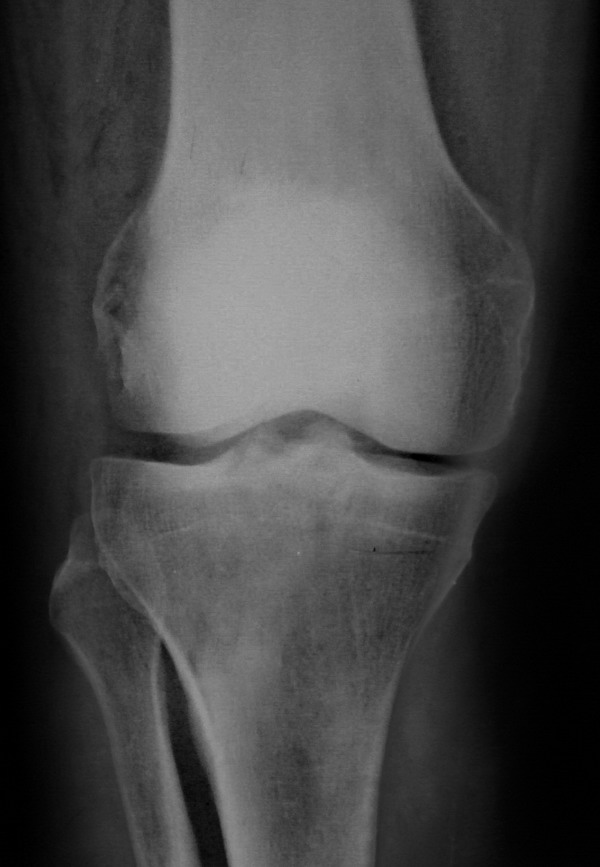

[Ortho] Нелеченный перелом Hoffa

Остеосинтез LCP пластиной